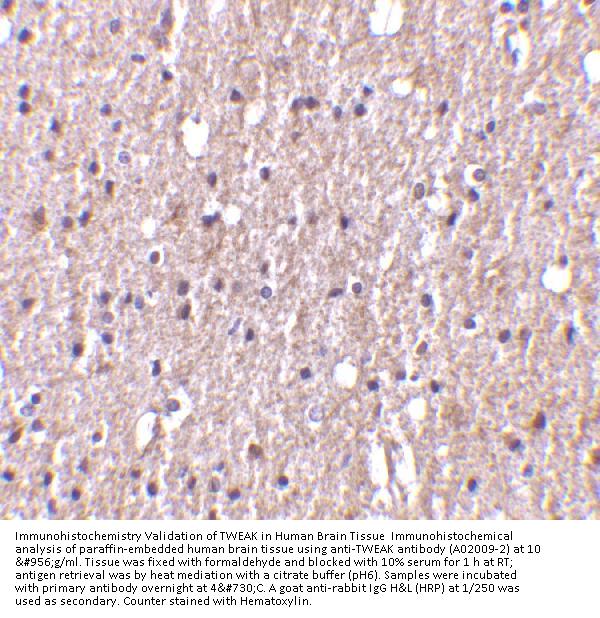

Applications WB, IF, ELISA, IHC-P

WB: 0.5-4 μg/mL; IHC: 5-10 μg/mL; IF: 20 μg/mL.

Antibody validated: Western Blot in human and mouse samples; Immunohistochemistry in human and mouse samples; Immunofluorescence in mouse samples. All other applications and species not yet tested. Optimal dilutions for each application should be determined by the researcher.